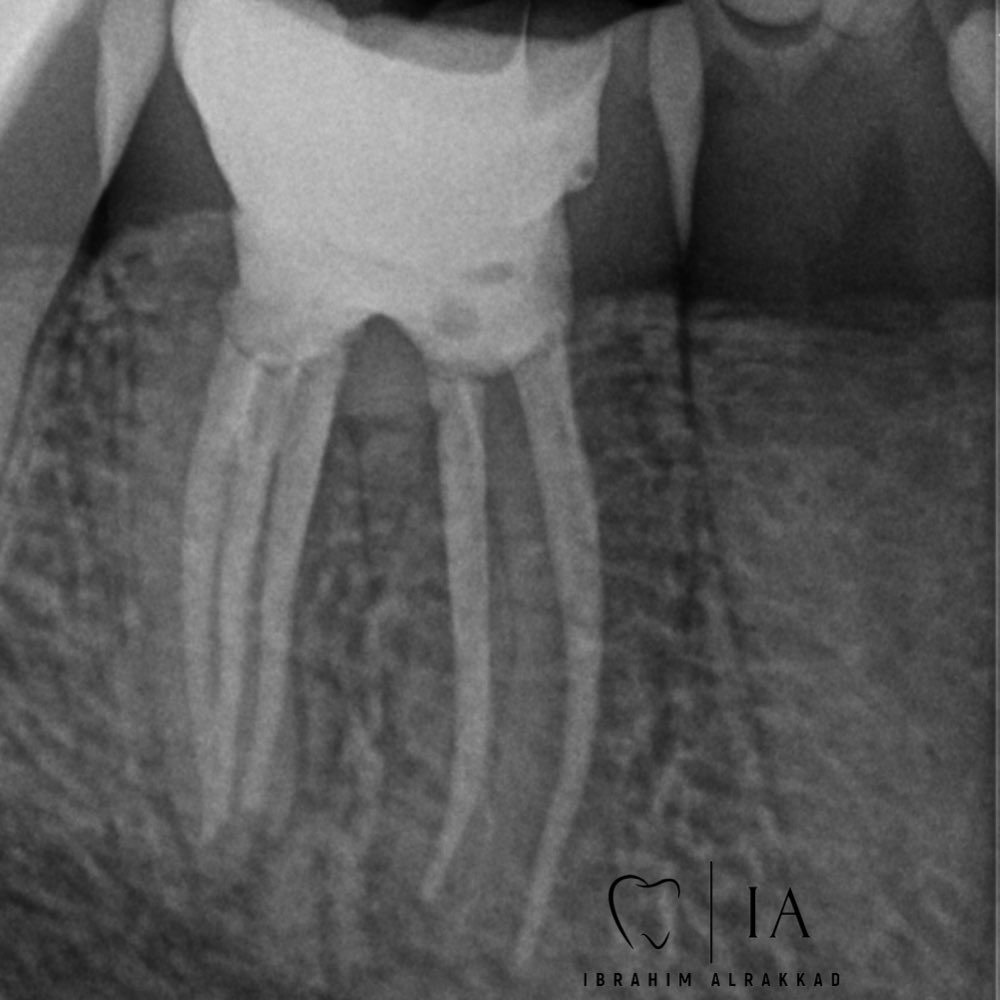

Tooth 46 Dx: previously initiated with SAP (Radix entomolaris) Tx:RCT 5 canals detected the extra one was Middle distal🔥 Look at the nice anatomy🤩🤩

Tooth 46

Dx: previously initiated with SAP (Radix entomolaris)

Tx:RCT

5 canals detected the extra one was Middle distal🔥

Look at the nice anatomy🤩🤩